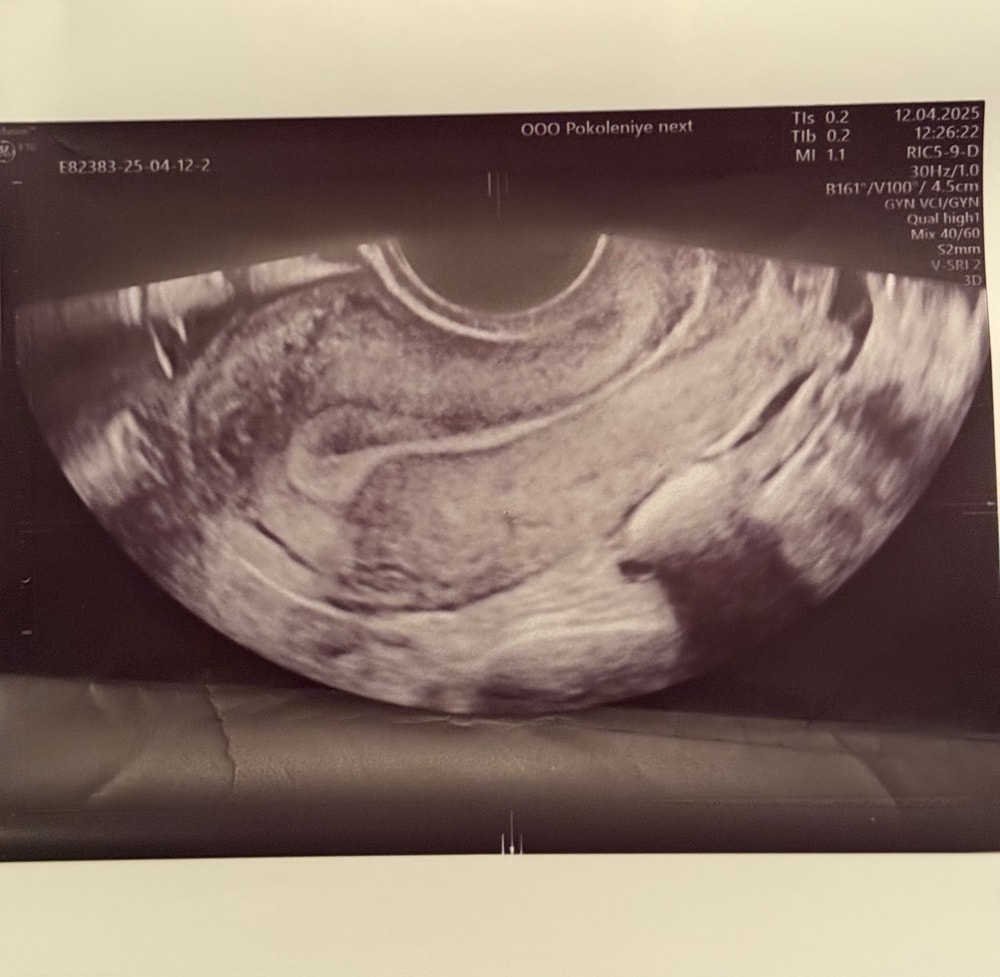

На узи написано то, что в заголовке. Также есть киста в регрессе. Может кто-то сталкивался с таким, что это значит гиперэхогенная структура ? Фото также прикр